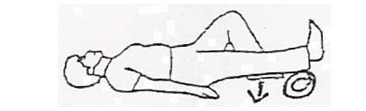

حوله لوله شدهای را زیر پاشنه بگذارید. زانو را ضمن فشار دادن پشت زانو به تخت کاملاً صاف کنید. 3 تا 5 ثانیه در این حالت بمانید، سپس استراحت کنید. این حرکت را 10 بار تکرار کنید.

زانو را صاف کنید، پا را روی حوله لوله شده بگذارید و پا را از موقعیت خمیده به سمت بالا بکشید. 5 ثانیه در این حالت بمانید. این حرکت را 10 بار تکرار کنید.